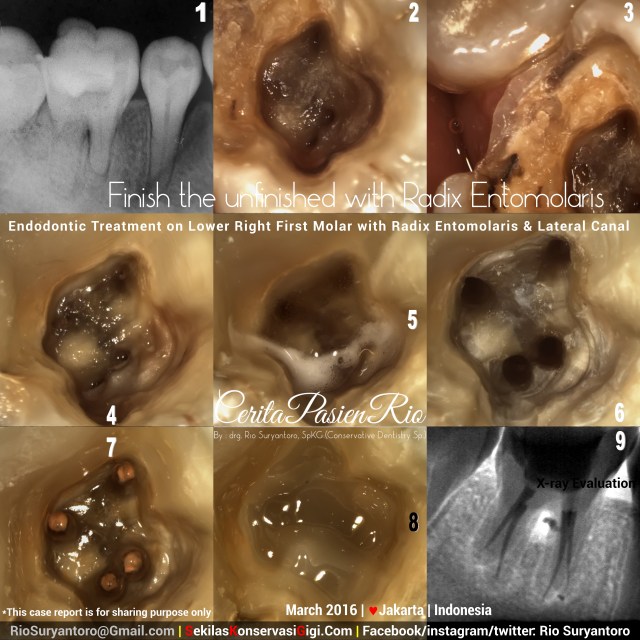

Endodontic treatment on lower right first molar with radix entomolaris

By definition, Radix entomolaris is the presence of an additional distolingual root in mandibular molars. The extra root is on the lingual side of the root.…

I got this patient with a big cavity which had been opened by another operator. The patient said that she had 4 visits and don’t know when is ended because she still feel pain while chewing.

The radiographic showed radiolucencies at the bifurcation area.

After taking informed consent. I build up the distal wall prior to root canal treatment. Shaping was done with ProtaperNext (Dentsply), coronally sealed with composite resin Z350 flowable (3MESPE).

Xray image taken with durr sensor 7.1 (60kV, 3mA, 0.03seconds).

Take a look at the presence of lateral canal at coronal third of mesial root.

Now we know why there is radiolucencies at the bifurcation.. 🙂